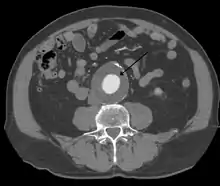

A 6.5 cm AAA with a 3 cm lumen

An aortic aneurysm can occur as a result of trauma, infection, or, most commonly, from an intrinsic abnormality in the elastin and collagen components of the aortic wall. While definite genetic abnormalities were identified in true genetic syndromes (Marfan, Elher-Danlos and others) associated with aortic aneurysms, both thoracic and abdominal aortic aneurysms demonstrate a strong genetic component in their aetiology.[13]